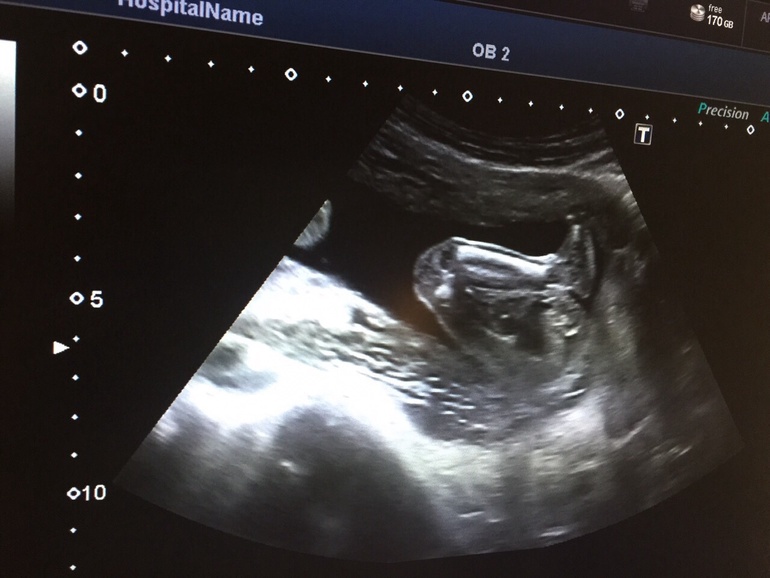

Во время УЗИ на мою просьбу сделать фото врач сообщила, что принтер у них совсем плохой; на просьбу сфоткать малыша на телефон с экрана, - что аппарат вообще плохой, хороший забрали, и что изображение такое, что только им понятно, и мне нечего там смотреть...

Однако, самое главное все же - здоровье! И здесь у нас все в порядке! :)))) Все органы ребеночка хорошо просматриваются, все параметры соответствуют сроку; количество вод нормальное. Расположен головкой вниз, что меня очень радует :)))) Врач сказала, что врядли уже перевернётся. Вес малыша, как сказали, 1919 грамм.